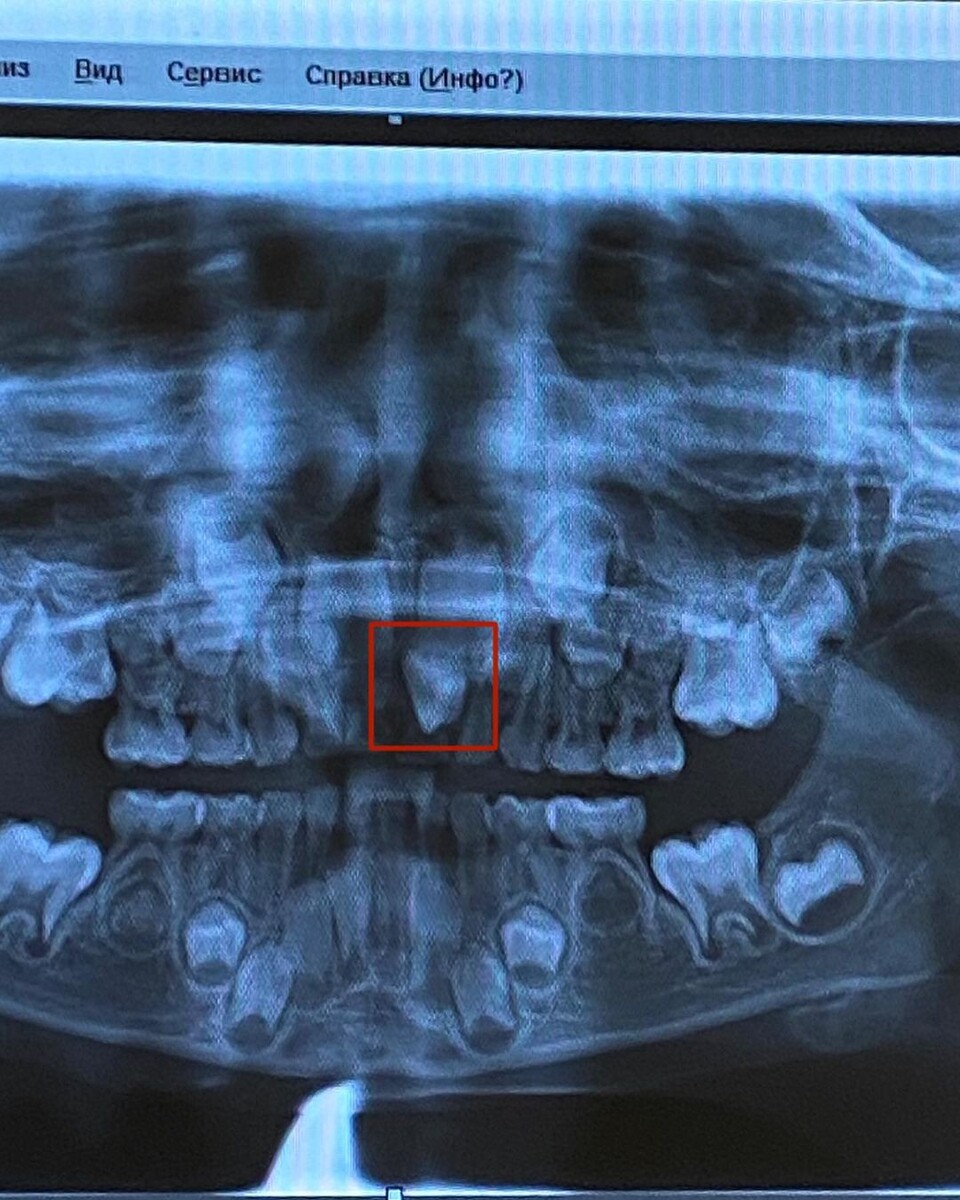

Я прошу сделать нам ортопантомограмму.

Стоматолог снова смотрит снимок: - Ну да, вот зуб «лишний», я советую вам удалять молочный, он мешается. Ох, у вас ещё и зачатков нижние пятёрок нет.. так интересно. 🤔

Вердикт: делать кт и смотреть где сверху зуб находится в проекции. И принимать решение об удалении молочного зуба. 🤷🏼‍♀️